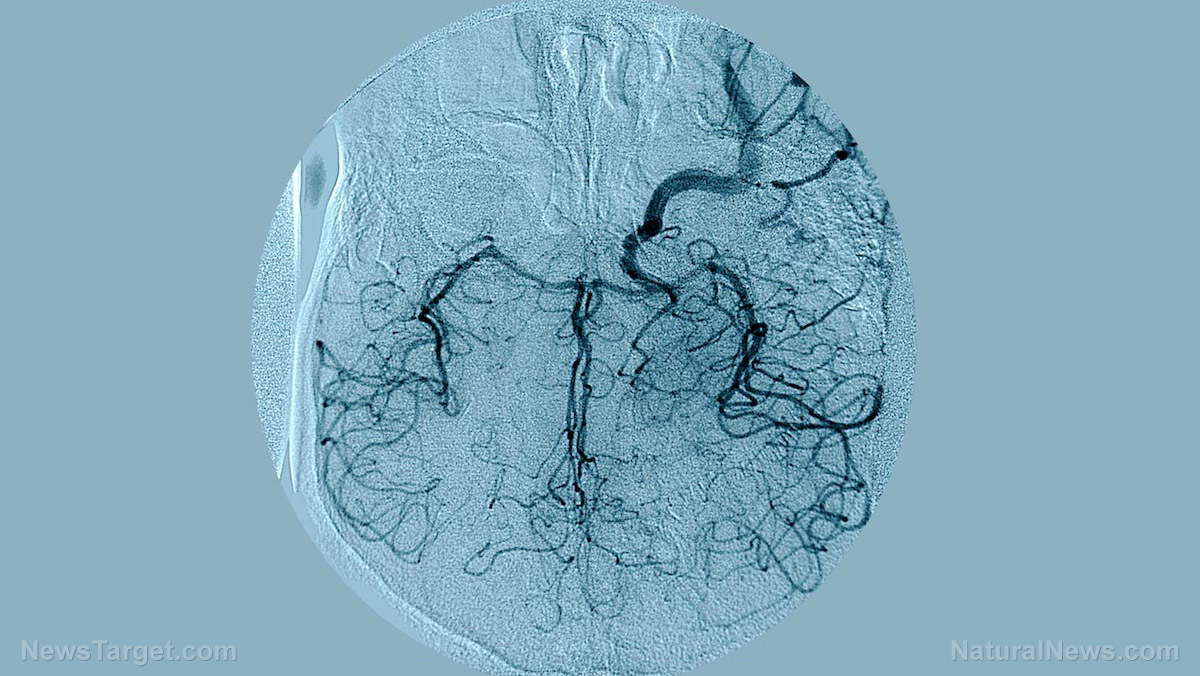

(Natural News) In a scene right out of a science fiction novel, scientists are now growing brains in a dish in an effort to further investigate mental health disorders. The “brains” are actually small three-dimensional spheroids containing model neural circuits, Independent.ie reports. The spheroids were grown from stem cells and developed through the same process that takes… |